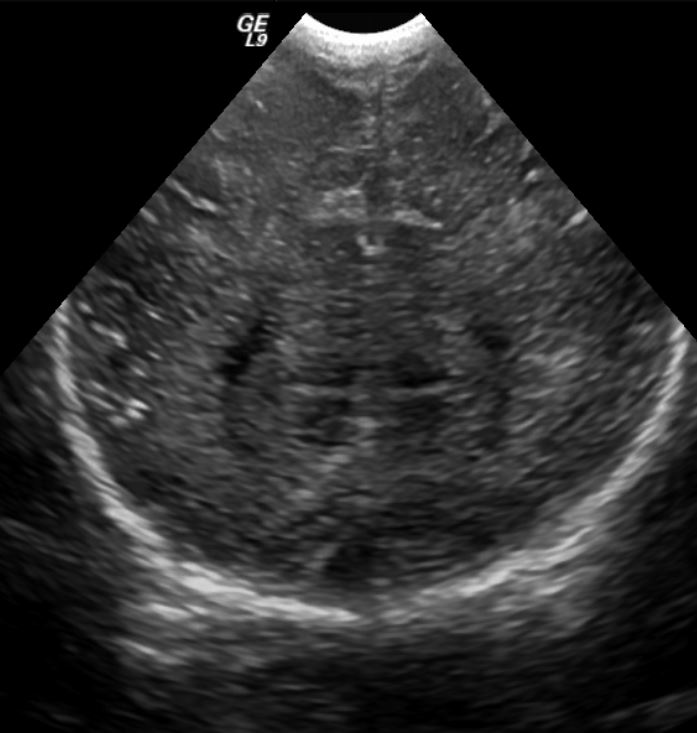

Section 1 Submit Findings Case149 Findings Brain The brain is immature. Yes No There is under-sulcation and open sylvian fissures. Yes No There is/are multiple hypoechoic areas in the periventricular white matter. Yes No There is/are multiple hyperechoic areas in the periventricular white matter. Yes No There is diffuse cerebral edema with diffusely increased echogenicity of the brain parenchyma and loss of grey white matter differentiation. Yes No The thalami/basal ganglia are hypoechoic. Yes No There is periventricular calcification. Yes No There is intra-parenchymal calcification. Yes No CSF spaces/ventricular system There is a prominence of the extra axial fluid spaces. Yes No There are debris/septations in the extra axial fluid spaces. Yes No There are debris/septations in the ventricles. Yes No There is a subdural collection on the right/left side. Yes No There is prominence of the ventricular system. Yes No There is an asymmetry of the ventricular system. Yes No There is a cavum septum pellucidum. Yes No There is a midline shift towards right/left. Yes No The choroid plexus is bulky/lobulated. Yes No There is a choroid plexus cyst measuring… Yes No There are debris/clots in the occipital horn. Yes No There is a posterior fossa cyst measuring… Yes No The tentorium is elevated/depressed. Yes No The lateral ventricle/s are dilated. Yes No The third ventricle is dilated. Yes No The 4th ventricle is dilated. Yes No There are pseudo cysts. Yes No Germinal matrix hemorrhage (Only in the premature infants): Please do not answer if the patient is a full term. There is a germinal matrix hemorrhage, consistent with a grade I hemorrhage. Yes No There is an intraventricular extension consistent with a grade II hemorrhage. Yes No There is an intraventricular extension with the dilatation of ventricles, consistent with a grade III hemorrhage. Yes No There is an intra-parenchymal extension, consistent with grade IV hemorrhage. Yes No On color Doppler examination, the Resistive index in the anterior cerebral artery is… There is a loss of the diastolic flow on the Doppler exam. Yes No There is altered vascularity on Doppler imaging. Yes No There is an AVM in the region of… Yes No